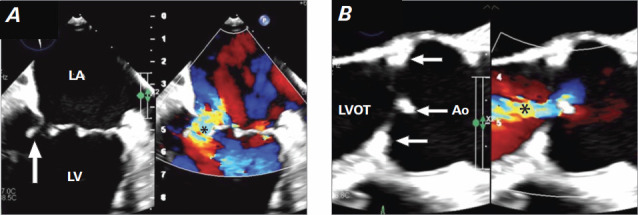

惠普尔病是一种罕见的全身性疾病,伴有体重减轻、腹泻和关节痛。无症状带菌很常见,但该病可因心脏受累而并发,并可能导致培养阴性的心内膜炎。该病的心脏表现可导致死亡。本报告介绍了一名 66 岁男性患者的病例,他患有 Whipple 病和双心室心力衰竭,并伴有心源性休克。在接受药物治疗后,成功置换了主动脉瓣和二尖瓣,病情得到显著改善。

Whipple disease is a rare systemic illness associated with weight loss, diarrhea, and arthralgia. Asymptomatic carriage is common, but the disease can be complicated by cardiac involvement and may result in culture-negative endocarditis. Cardiac manifestations of the disease can lead to death. This report presents the case of a 66-year-old man with Whipple disease and biventricular heart failure with cardiogenic shock. Medical therapy followed by successful replacement of the aortic and mitral valves resulted in substantial improvement.